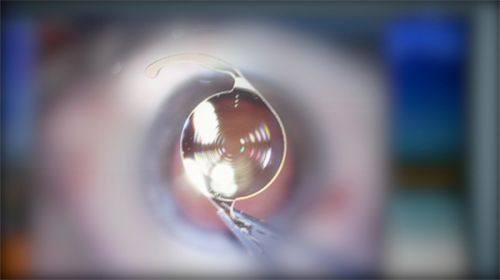

1、蔡司3.0全飞秒激光近视手术价格:13800元起。这种手术方式切口小,修复快,对角膜的损伤相对较小。在东莞市,这样的价格能享受到如此精良的技术和优质的服务,是非常划算的。医院采用的是精良的蔡司设备,医生也具备专精的操作技能,能够根据患者的具体情况制定个性化的手术方案。

东莞友华普惠眼科医院是广东省东莞市一家备受认可的正规眼科医院。它拥有进口的医疗设备,这些精良的设备能够为正确的诊断和治疗提供有力的支持。比如在近视手术中使用的蔡司设备,能够严谨地进行手术操作,提高手术的安心性和有效性。

医院的医生团队也非常强大。其中,李鹏医生是友华普惠眼科·近视矫正手术中 心副主医师,德国蔡司全飞秒认证骨干医生。他从事眼科工作20余年,曾任国内人民解放军联勤保护部队第九二四 医院(原第一八一医院)眼科副主事。李医生擅长全飞秒、半飞秒、准分子激光手术,还曾参与中山大学中山眼科中 心科研项目,在国级眼科专精期刊、学术论坛发表论文多篇。他的手术技艺娴熟,获得了业界同行的高度认可。